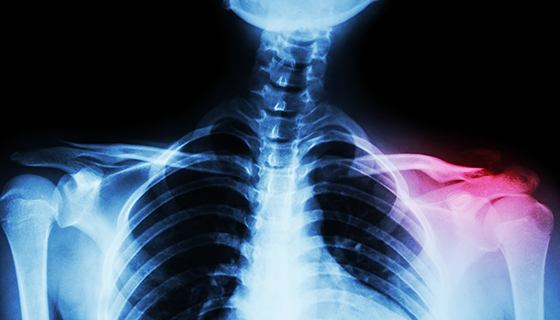

美国四分卫亚伦·罗杰斯(Aaron Rodgers)在2017年对阵明尼苏达维京人队的比赛中摔倒并摔断了右锁骨。通常,锁骨恢复大约需要12周左右。但是,绿湾的球迷们期望球员很快能够真正康复,并帮助球队赢得另一个赛季。

骨是一种压电材料,这意味着将其放置在应变下时会产生一点点的电力。这些电力的震动会促进骨骼生长和愈合因子,这就是为什么静电是有益的治疗方法的原因。